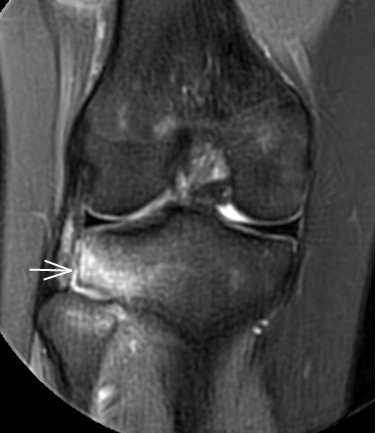

2. 運(yùn)動(dòng)后“打軟腿”——韌帶的“斷弦危機(jī)”

場景:打球急停后膝蓋不穩(wěn),走路像“踩棉花”

MRI偵查:揪出前交叉韌帶斷裂(呈“波浪狀”或連續(xù)性中斷)、內(nèi)側(cè)副韌帶損傷,防止關(guān)節(jié)“脫軌”

(內(nèi)側(cè)副韌帶損傷)